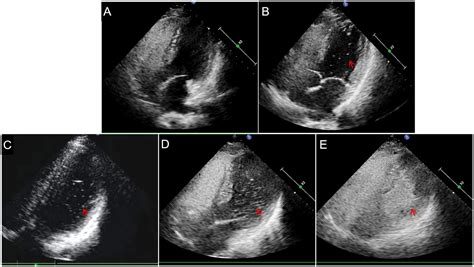

Echocardiography Visualizes blood flow and identifies structural septal defects.

Bubble Study Uses agitated saline to track the movement of bubbles across heart chambers.

⚠️ Note: A bubble study is particularly effective at identifying a PFO or atrial septal defect, as the microbubbles act as a contrast agent that can be easily visualized crossing the septum on an echocardiogram.